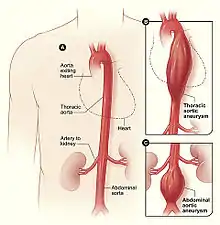

| Figure A shows a normal aorta. Figure B shows a thoracic aortic aneurysm (which is located behind the heart). Figure C shows an abdominal aortic aneurysm located below the arteries that supply blood to the kidneys. | |

An aortic aneurysm is an enlargement (dilatation) of the aorta to greater than 1.5 times normal size.[1] They usually cause no symptoms except when ruptured.[2] Occasionally, there may be abdominal, back, or leg pain.[3] The prevalence of abdominal aortic aneurysm ("AAA") has been reported to range from 2 to 12% and is found in about 8% of men more than 65 years of age.[4] The mortality rate attributable to AAA is about 15,000 per year in the United States and 6,000 to 8,000 per year in the United Kingdom and Ireland. Between 2001 and 2006, there were approximately 230,000 AAA surgical repairs performed on Medicare patients in the United States.

The etiology remains an area of active research. Known causes include trauma, infection, and inflammatory disorders. Risk factors include cigarette smoking, advanced age, dyslipidemia, hypertension, and coronary artery disease. The pathophysiology of the disease is related to an initial arterial insult causing a cascade of inflammation and extracellular matrix protein breakdown by proteinases leading to arterial wall weakening.[5] They are most commonly located in the abdominal aorta, but can also be located in the thoracic aorta. Aortic aneurysms result from a weakness in the wall of the aorta and increase the risk of aortic rupture. When rupture occurs, massive internal bleeding results and, unless treated immediately, shock and death can occur.

Aortic aneurysms are classified by their location on the aorta.

- Thoracic aortic aneurysms are found within the chest; these are further classified as ascending, aortic arch, or descending aneurysms.

- Abdominal aortic aneurysms, "AAA" or "Triple A", the most common form of aortic aneurysm, involve that segment of the aorta within the abdominal cavity. Thoracoabdominal aortic aneurysms involve both the thoracic and abdominal aorta.